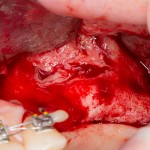

Сначала убираем все грануляции и измененные ткани. На перфорации слизистой не обращаем внимания — с ними разберемся позже:

7  8

Как видите, после удаления «всего лишнего» получился значительный дефект? Большинство хирургов на этом этапе действительно приунывают и сворачивают операцию, мотивируя это тем, «что в данных условиях невозможно что-то восстановить».